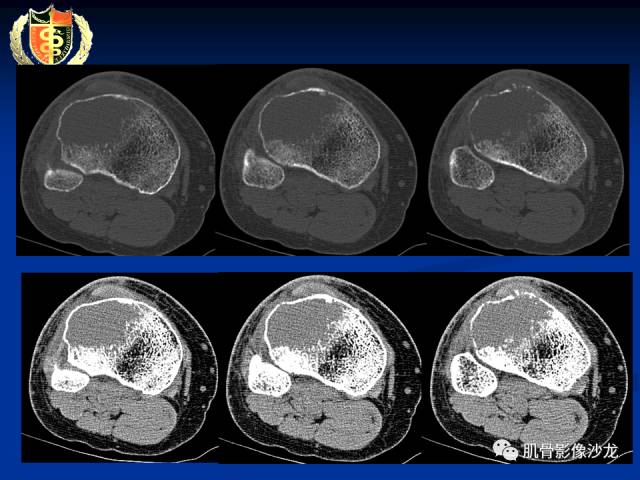

骨淋巴瘤及软骨肉瘤两例CT及MR影像表现

内部密度和信号比较均匀,无钙化,无骨膜反应,骨质破坏边缘不清晰,软组织较明显,弥散受限,首先不能排除淋巴瘤

胫骨近端骨质破坏,边缘不清,破坏边模糊,骨皮质不完整,可见软组织肿块突破骨皮质外,病灶累及关节面下,无关节内累及,MRI病灶呈T2WI高信号,信号均匀,考虑:恶性肿瘤性病变,淋巴瘤先考虑,转移瘤及其他待排